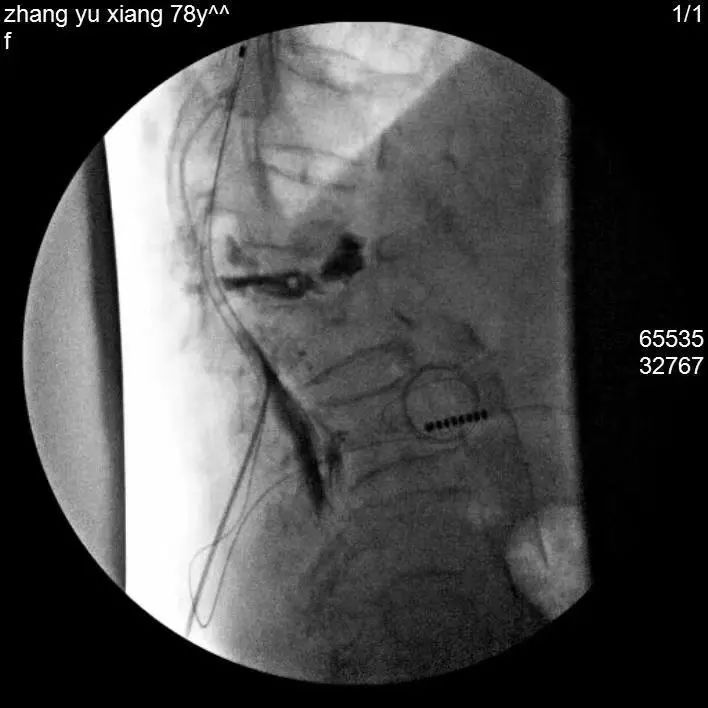

经过细致的检查评估,曹玮主任决定采用目前国际上较为成熟的“脊髓电刺激”疗法来为张阿姨治疗糖尿病足性疼痛,并避免截肢。脊髓电刺激治疗是一种微创疼痛治疗技术,它是在脊髓的硬膜外后间隙插入一根电极,通过电刺激阻断疼痛信号的传导,同时可调控交感神经以改善糖尿病足的末梢血运循环。但是由于张阿姨长期患有类风湿性关节炎,脊柱及四肢严重畸形,无法俯卧位,且椎管多节段狭窄,常规操作无法将电极植入脊椎预定位置,为治疗带来了很大难度。为此,曹玮主任及其团队决定创新采用血管鞘介入技术辅助电极植入,用穿刺针成功引入导丝、导管及血管鞘,通过血管鞘成功建立电极植入通道,之后成功将电极植入至硬膜外脊髓背侧预定的相应刺激区域。在术中测试及术后随访中,张阿姨表示下肢疼痛明显减轻。

经穿刺针置入导丝引导,置入导管及鞘管、引导电极植入